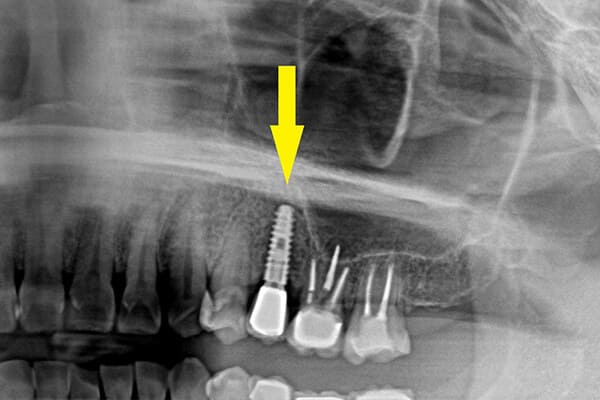

インプラント部位のレントゲン写真

前歯の歯根がボロボロになり、

周囲の骨が大きく吸収されてしまいました。

上のレントゲン写真を示した症例で、骨移植後、インプラントを埋入し、上部構造(歯の部分)がはいったところ。